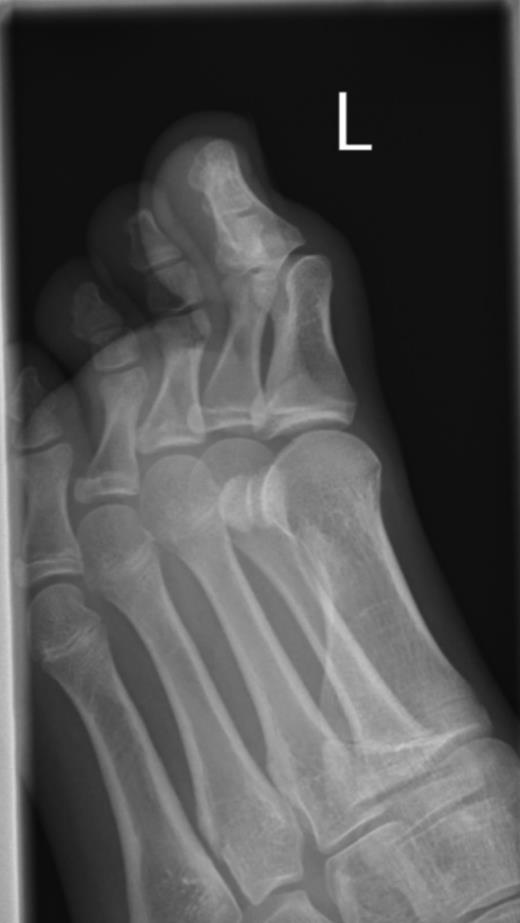

Plain radiographs showed no bony injuries, but the IPJ was subluxed in a plantar-flexed position (Fig. 1). An urgent ultrasound scan confirmed a full thickness rupture of the extensor hallucis longus (EHL) tendon at its insertion into the distal phalanx and evidence of a healing tear to the dorsal joint capsule (Fig. 2).